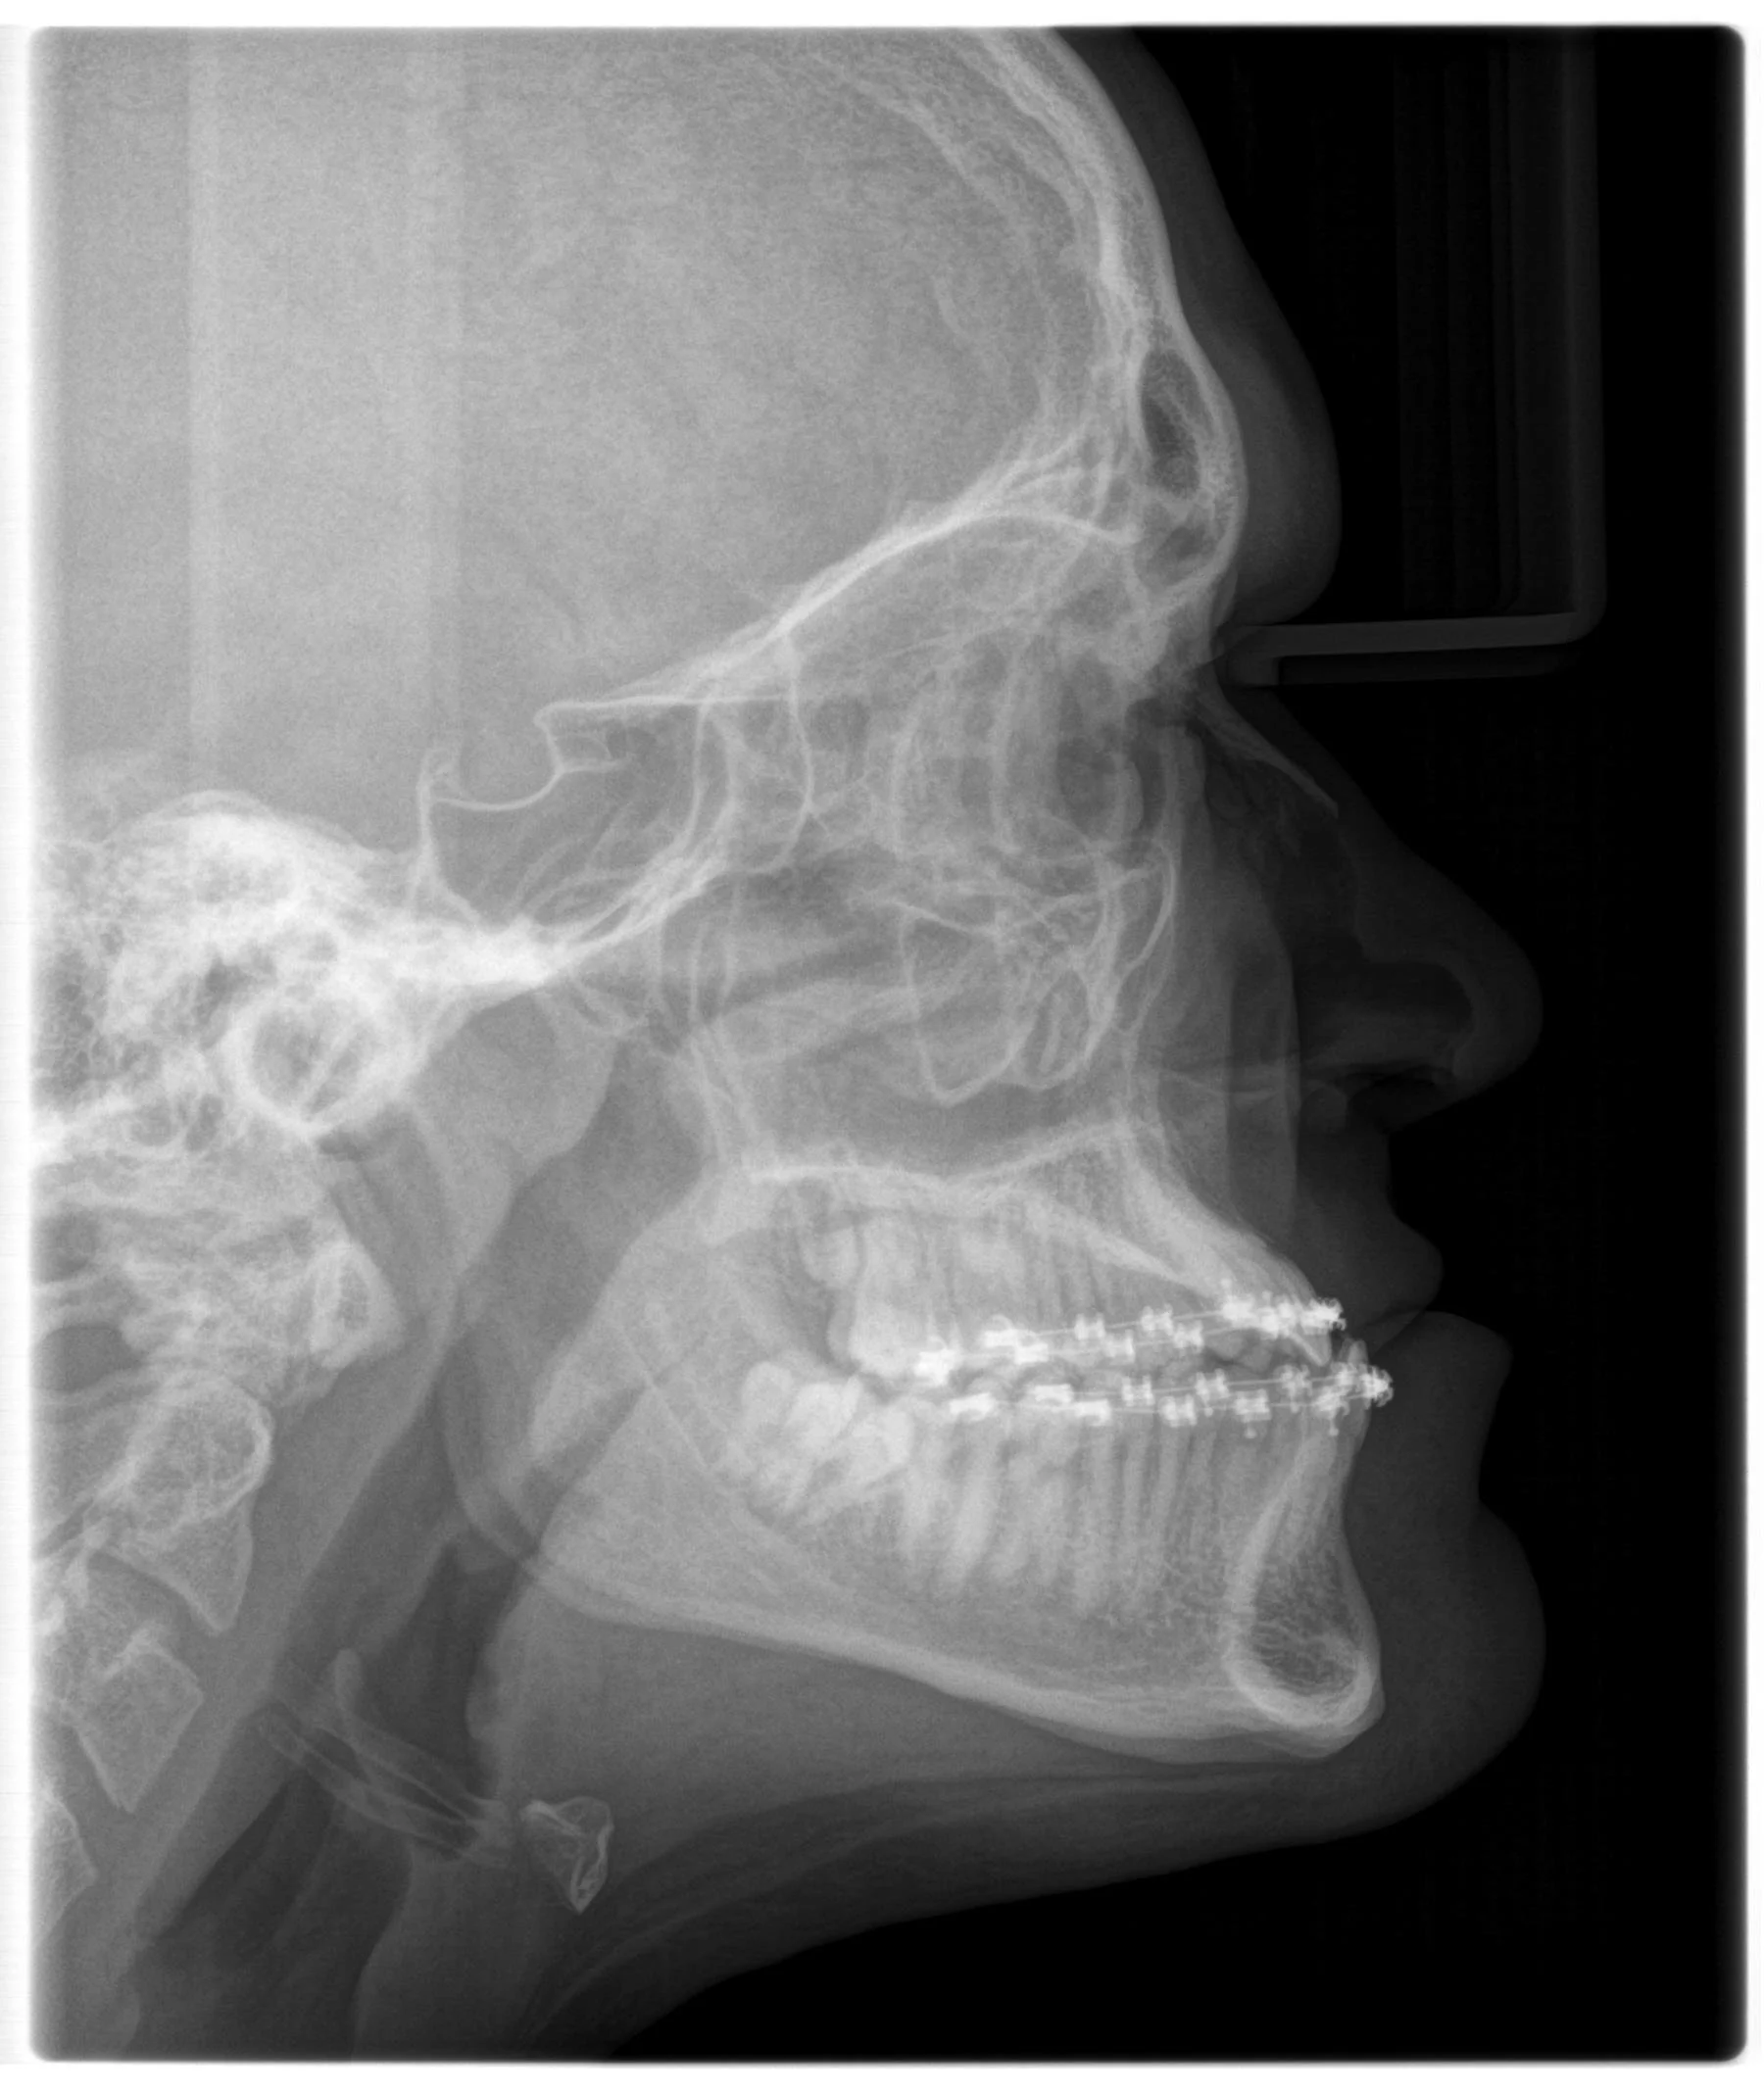

Subject with Class III jaw growth

Same subject 4 years later: Upper incisors are proclined, and lower incisors occlude in front of the upper incisors.